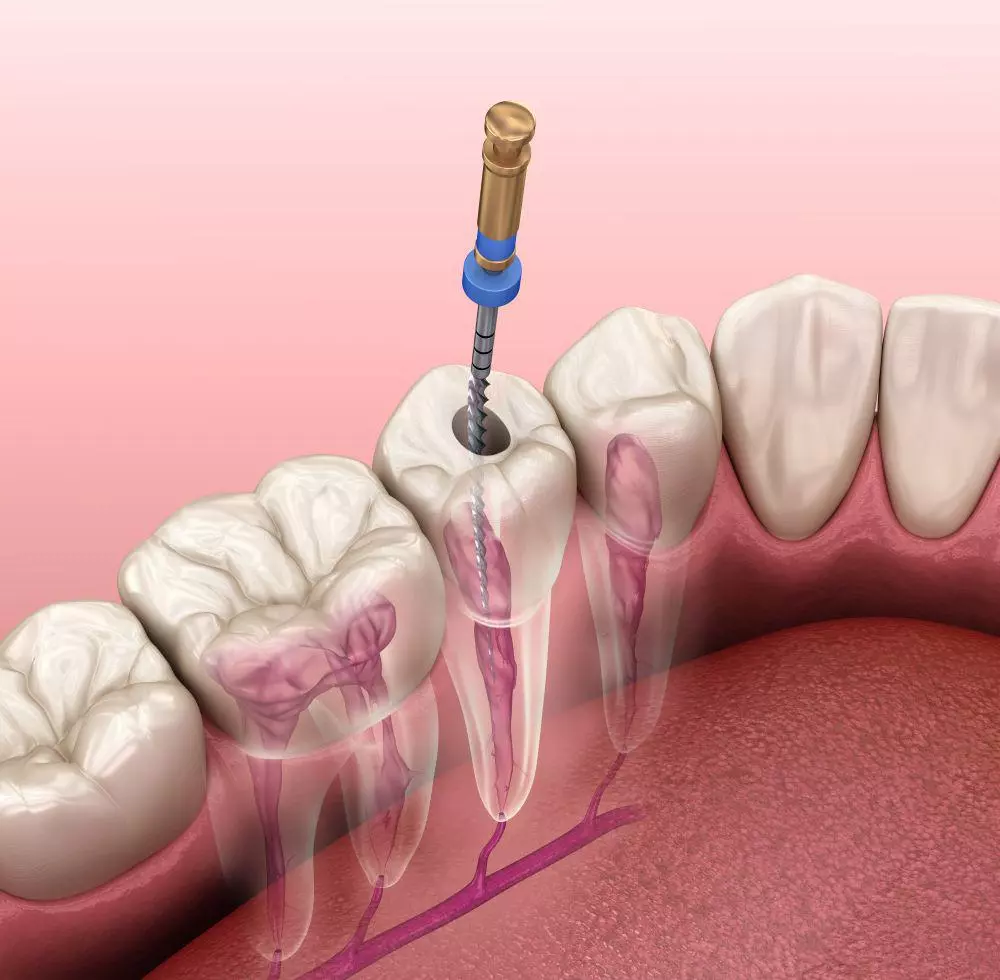

Nos enfocamos en una atención integral de tu tratamiento, por ello contamos con especialistas en Periodoncia (para atender correctamente tus encías) Endodoncia (tratamientos de conductos) Ortodoncia (para alinear tus dientes).